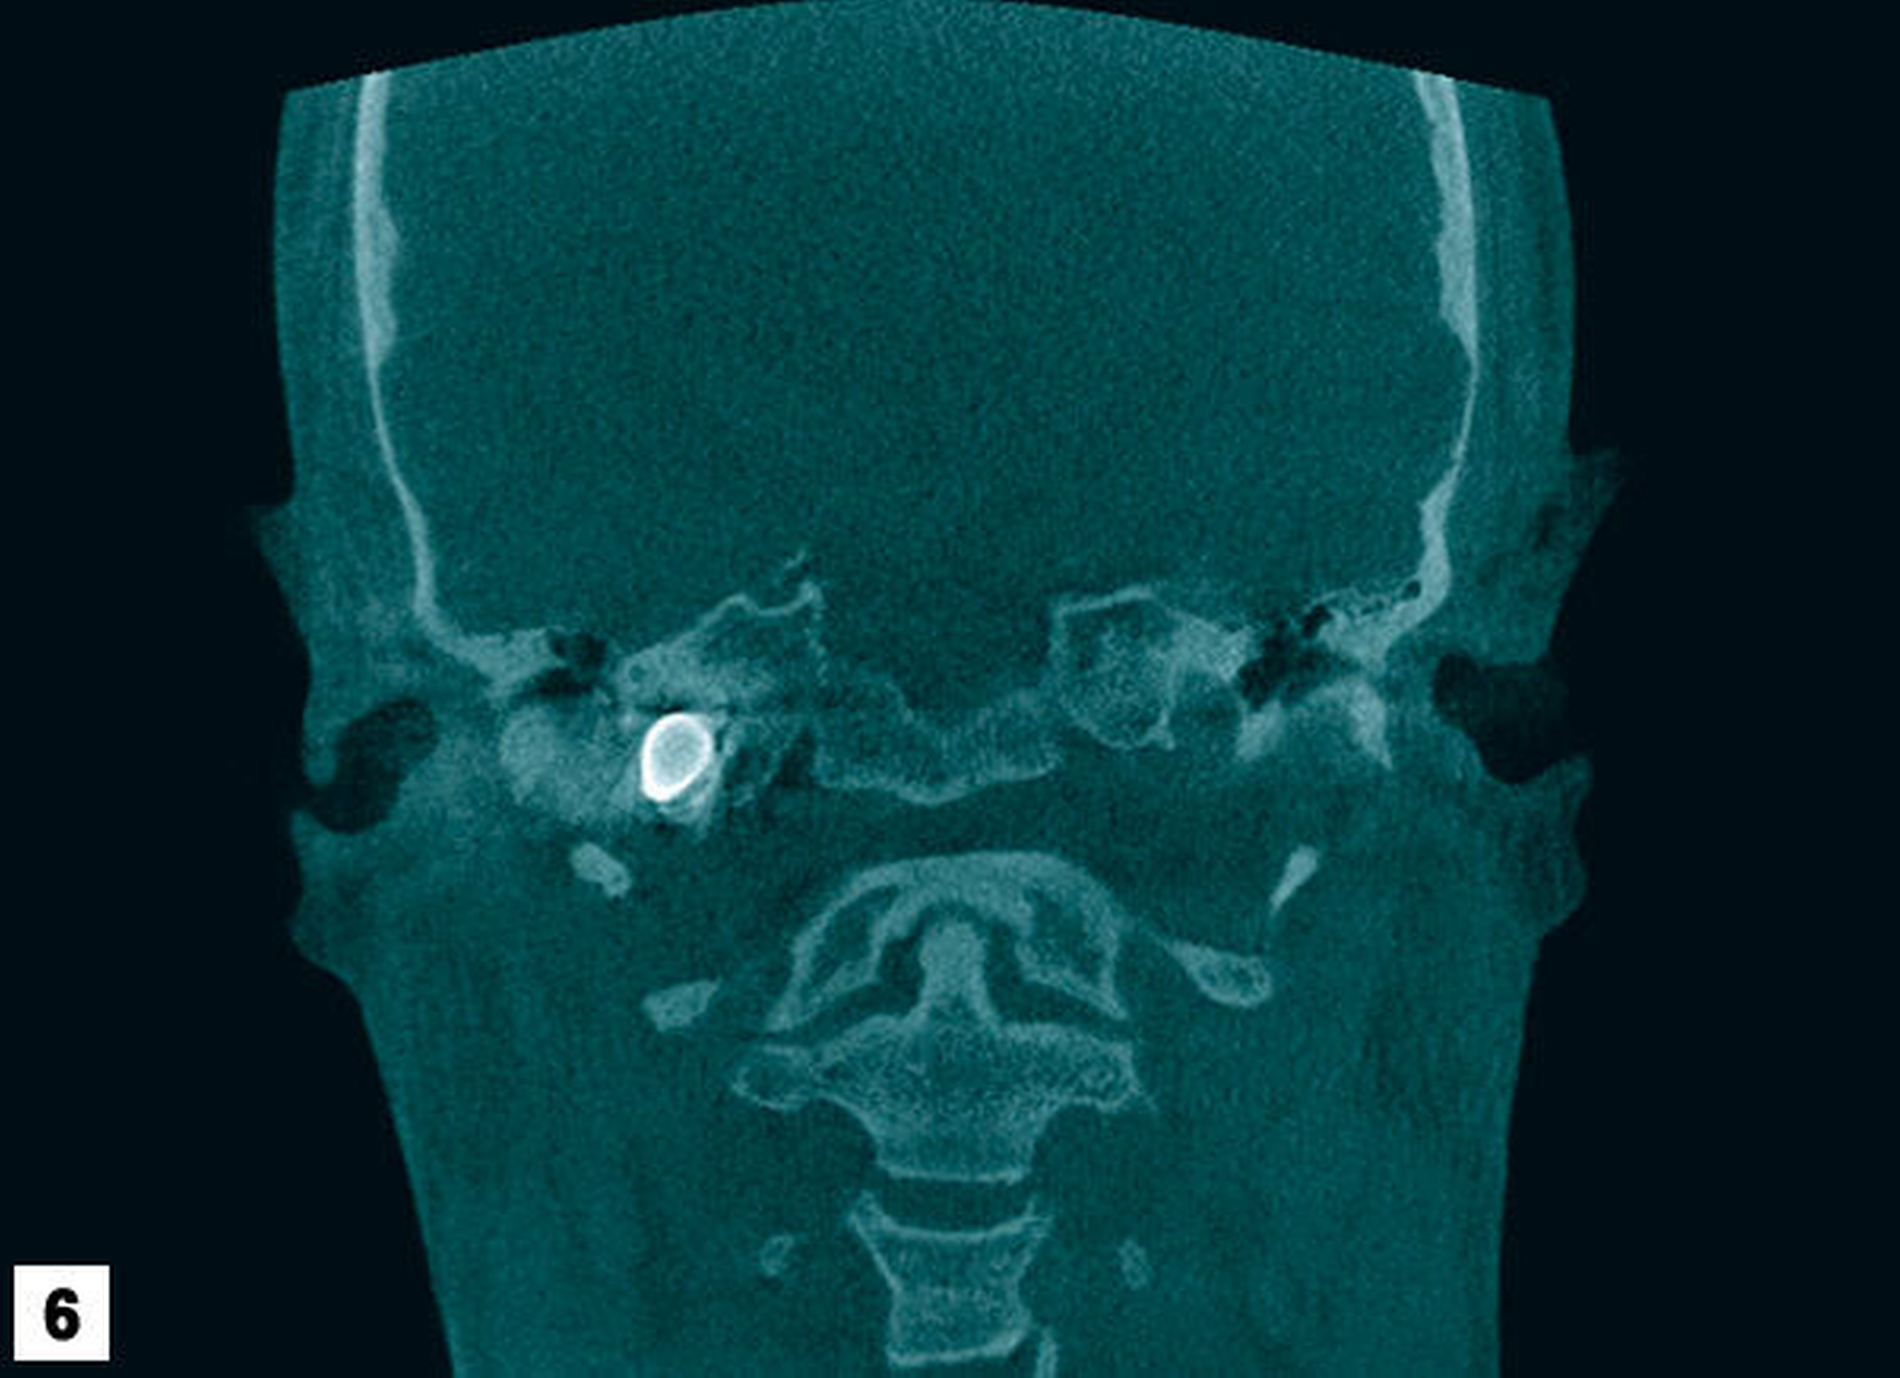

Zur weiteren Lokalisation in der dritten Ebene wurde eine Digitale Volumentomografie veranlasst. Diese Bilder zeigten neben einer großen Osteolyse apikal des Zahns 37 und deutlicher Schleimhautschwellung im Bereich der Sinus maxillares und ethmoidales einen metalldichten Fremdkörper im Bereich der Schädelbasis mit einer Ausdehnung von circa 7 mm x 38 mm mit einer projektiltypischen Form (Abbildungen 4 bis 6). Die Recherche lässt vermuten, dass dieses Projektil als Munition für ein Automat Kalaschnikow 47 Sturmgewehr (AK 47, wahre Größe der Kurzpatrone M 43 = 7,62 mm x 39 mm) passt.